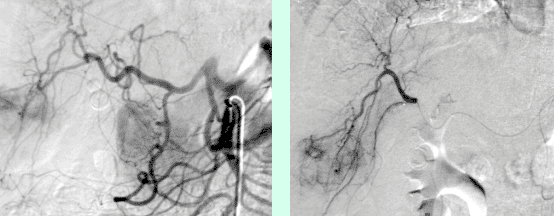

Ist der Tumor für die Embolisation geeignet, und die Leberfunktion gesichert, geschieht der Eingriff an der Abteilung für Kardiovaskuläre und Interventionellen Radiologie. Eine kleine Punktionsstelle in der Leiste reicht, um einen Katheter so einzuführen, dass seine Ende genau vor dem Lebertumor platziert werden kann. Die genaue Platzierung geschieht mit sogenannten Mikrokathetern, welche bis in die kleinsten Gefäße, in sogenannter „superselektiver Technik“, geführt werden können. Dies ist für den Erfolg der Behandlung besonders wichtig. Dann werden von dieser „Abschußrampe“ kleinste Kugeln, sogenannte Partikel, in einer Größe von 300–900μ in die zum Tumor führenden arteriellen Gefäße eingeschwemmt, bis sie diese völlig blockieren und ausfüllen. Danach wird ein geringe Menge „Glubran“, ein Gewebeklebstoff eingebracht, der bewirken soll, daß die Verstopfung der Tumorgefäße auch erhalten bleibt. Mittels moderner angiographischer Techniken kann der Erfolg der Behandlung sofort kontrolliert und bewertet werden. Falls mehrere arterielle Äste zum Tumor führen, können diese alle einzeln, superselektiv, mit den Mikrokathetern erfasst und behandelt werden.

© Universitätsklinik für Radiologie und Nuklearmedizin

Abbildung 1: Übersichtsangiographie der Leber und superselektive Lage des Mikrokatheters vor Embolisation.

Abbildung 2: Angiographiekontrolle nach Embolisation. Die Tumor versorgenden Gefäße sind verschlossen.